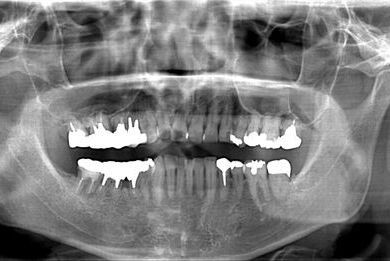

インプラントの症例写真 IMPLANT

インプラント治療+セラミック治療+歯肉歯槽骨整形術

| 性別/年齢 | 男性 / 47歳 | ||||||||||||||||||||||||||||||||

| 主訴 | 悪いところの治療と、歯をきれいにしたい。 | ||||||||||||||||||||||||||||||||

| 治療方針 | 右下奥、保存不能な歯を抜歯し、インプラント治療にて、機能的・審美的回復を行う。 | ||||||||||||||||||||||||||||||||

| 治療内容 | インプラント2本、メタルボンドセラミッククラウン9本(メタルボンド用土台6本)、ハイブリッドセラミッククラウン2本(セラミック用土台2本)、ハイブリッドセラミックインレー5本、歯肉歯槽骨整形術 | ||||||||||||||||||||||||||||||||